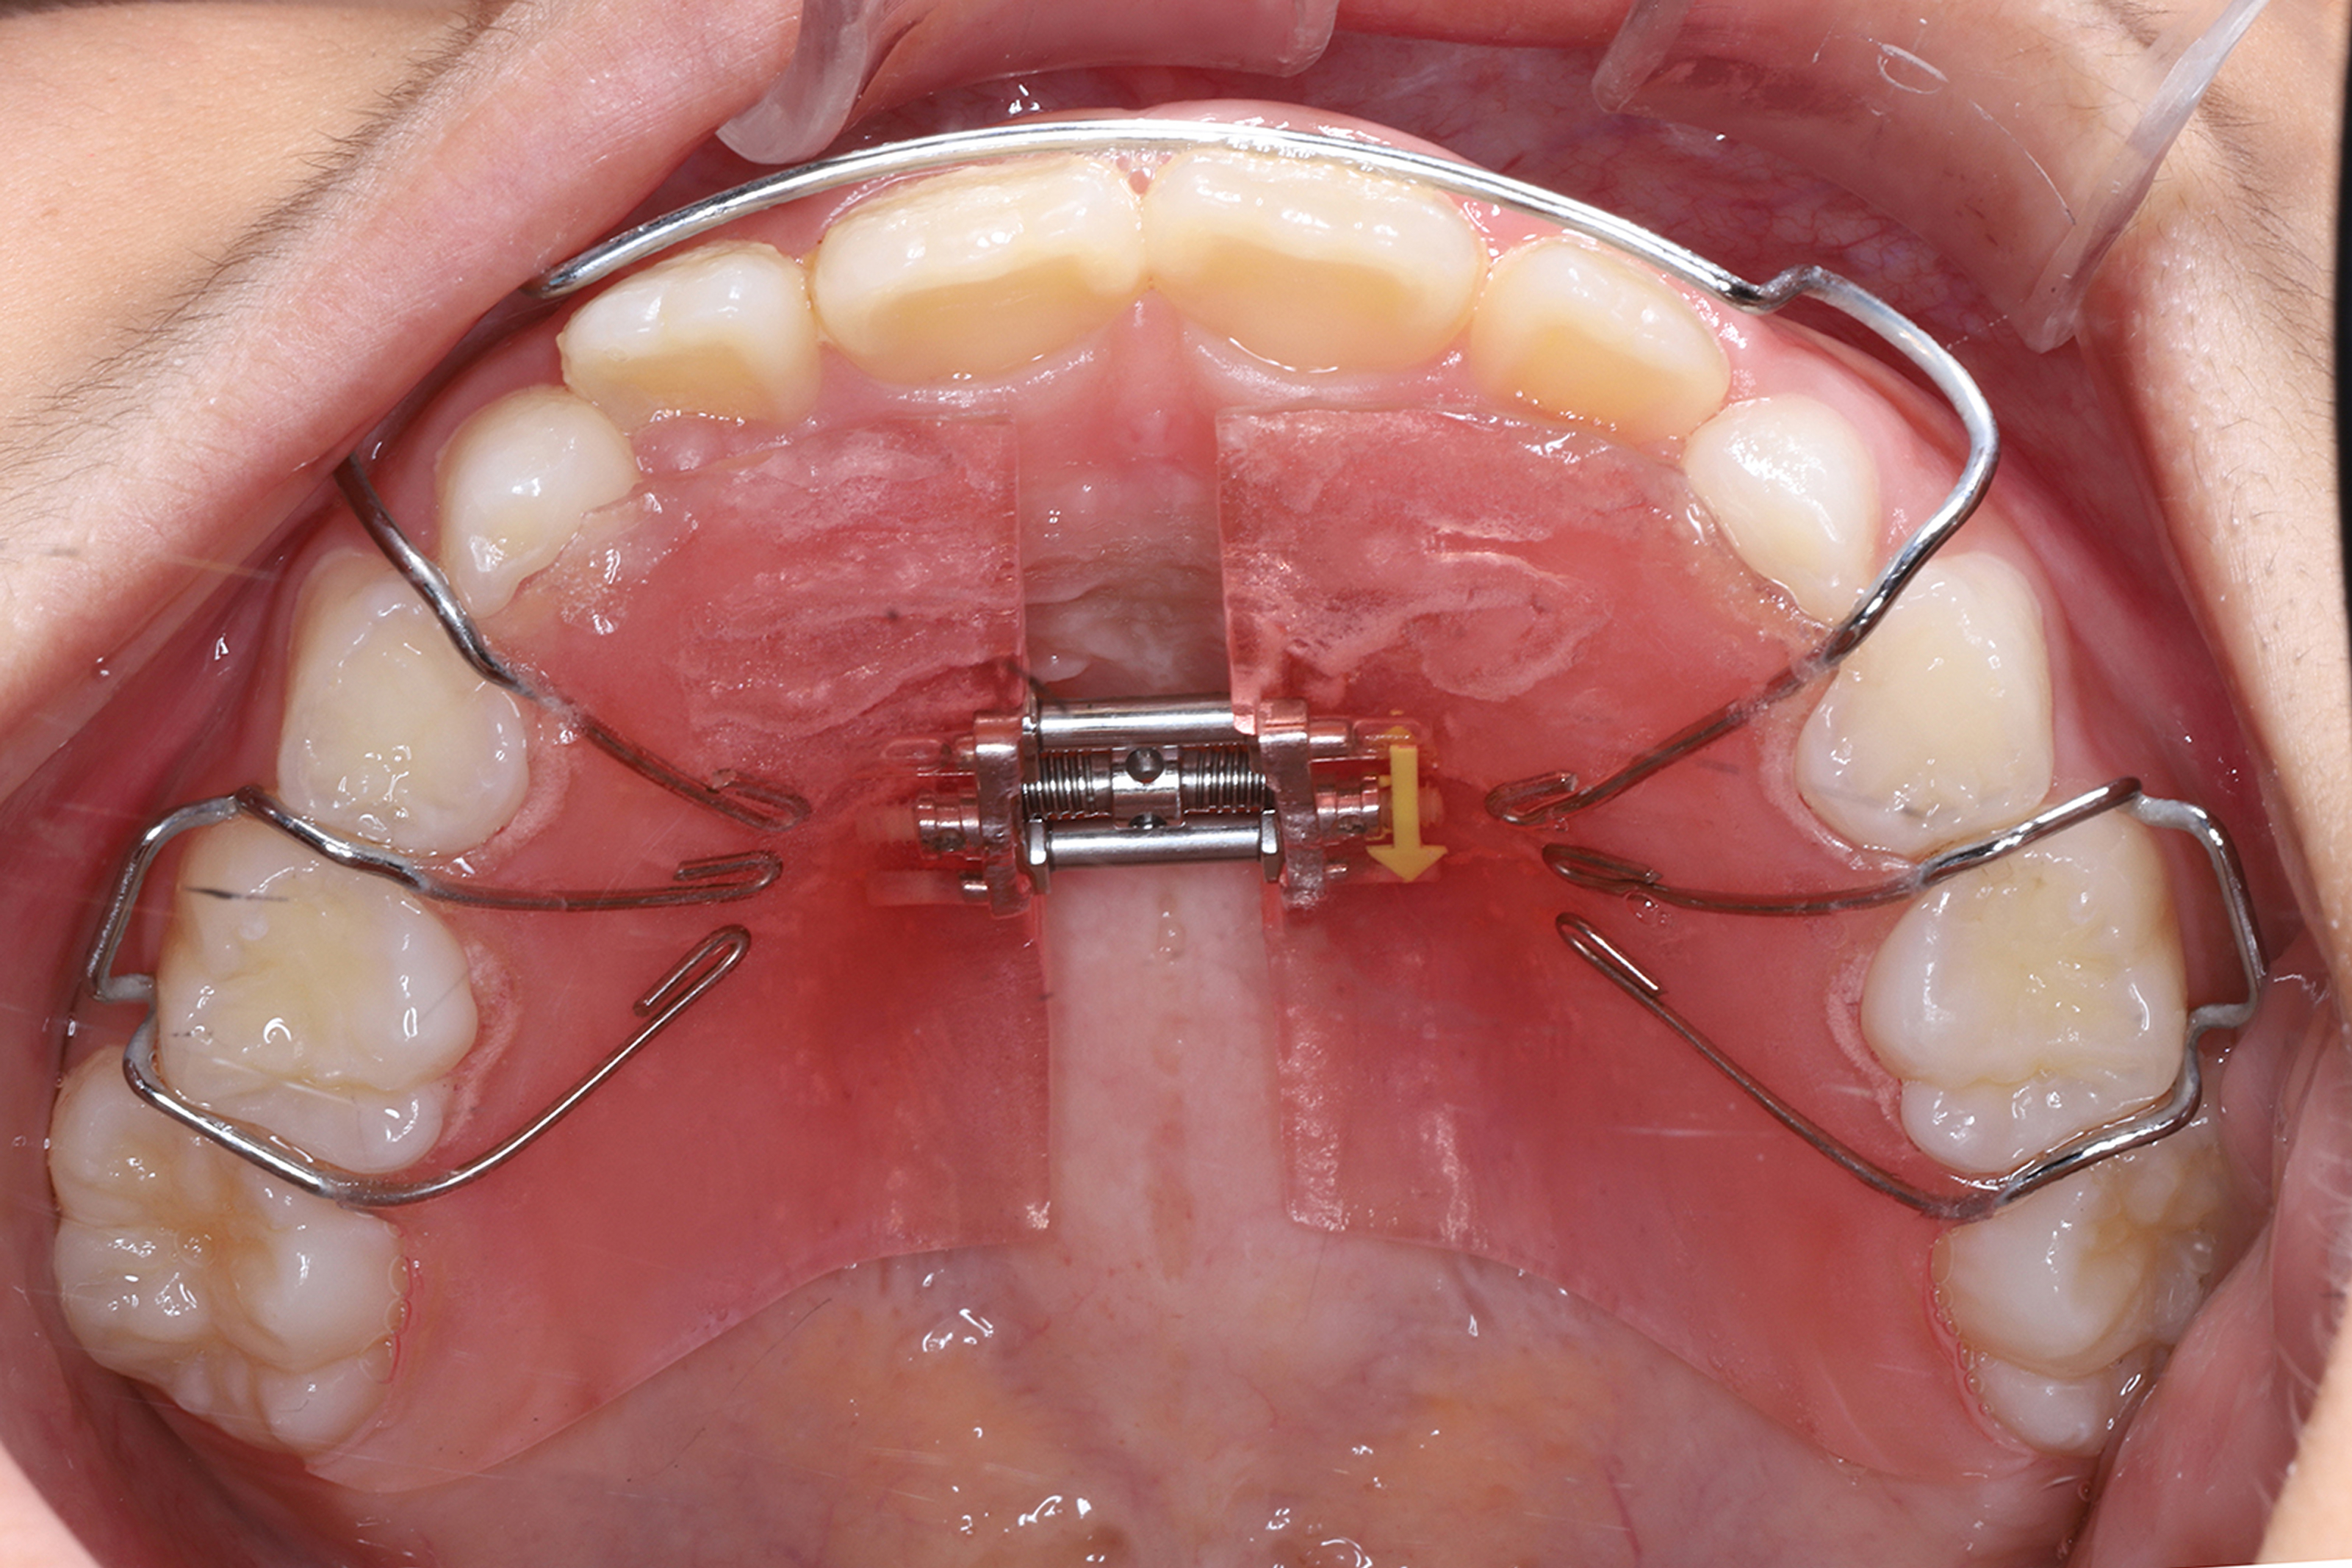

日本で行われている拡大床治療にも色々な方法がありますが当院での特長は最初に永久歯に生え替わる上下4本の前歯を奥歯の生え替わりが始まる前までに顎を拡大してきれいに並べることです。そのため拡大床治療の期間は小学校1年生頃から4、5年生頃までの間に限定しており、それまでに目的が達成できない場合には別の治療法に移行します。またゆっくりスペースを獲得するようにしているのも特長で2週間に1回ネジを回すようにしています。一般的には1週間にⅠ回ないし2回ネジを回すことが多いようです。ゆっくり進めるので一日の装着時間はお家にいるときと寝ている間だけにしています。学校や自宅以外での装着はせずゆっくり拡大していくので治療期間が長くなりますが後戻りは少なく確実になります。治療開始時期が大切ですので時期を逸した場合には拡大床治療は行いません。一般的に拡大床治療の評判が悪いのは開始時期が遅く、いつまでも治療を長引かせ治らないことによるものが多いようです。 拡大床治療はスペースを作って永久歯がならぶスペースを作ることが目標ですので細かい歯の向きや角度まで整えられないこともあります。そんな場合には別の矯正治療が必要になります。

拡大床治療で顎のスペースを拡げられるのは11歳くらいまでです。そのため個人差はありますが遅くても小学校2年生までに始めなければなりません。下の前歯が生え替わりはじめた頃から下の前歯が4本、上の前歯が2本生え替わる頃までが始め時です。すでに上下4本とも生え替わってしまった場合にはすでに遅いことが多くあります。

拡大床治療は矯正治療ではありませんので完璧にきれいな歯ならびにできるわけではありません。また治療期間も長くなり期間限定の治療法ですので小学校の高学年になってから始めるのには向いていません。また拡大床治療で歯を並べる顎は拡がりますがエラの張った大きな顔になるわけではありません。歯を支える骨は歯槽骨、下顎全体は下顎骨と言って解剖学的には別の骨と考えられています。エラが張った大きな顎になるのは遺伝的な要素や咬む力が大きく影響します。拡大床治療を行ったからといって顎全体が大きくなるわけではありません。